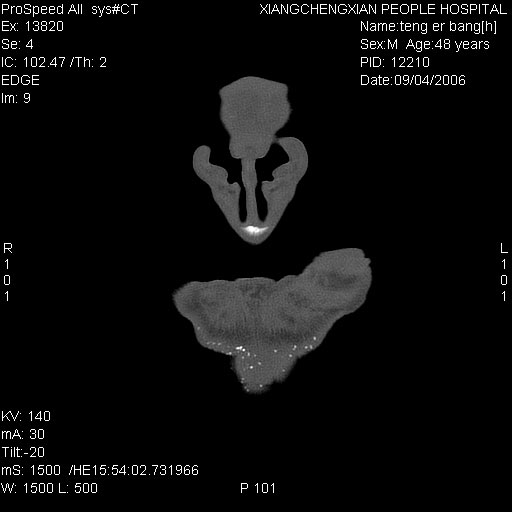

患者,男,以头面部外伤后头疼1小时为主诉入院,患者1小时前被他人打伤头部及左侧面部,眼睑无水肿,左侧面部肿胀压疼,未触及骨擦音。专科检查:耳鼻喉未见异常。

ct:平扫+冠扫:双侧鼻骨对比,冠扫s6#示右侧鼻骨尖部可见线状低密度影,边缘光滑,并见硬化.软组织未见肿胀.

诊断意见:鼻额缝(鼻骨与上颌骨额突缝),但个别同志认为是骨折.因此请同行们会诊.多谢了!